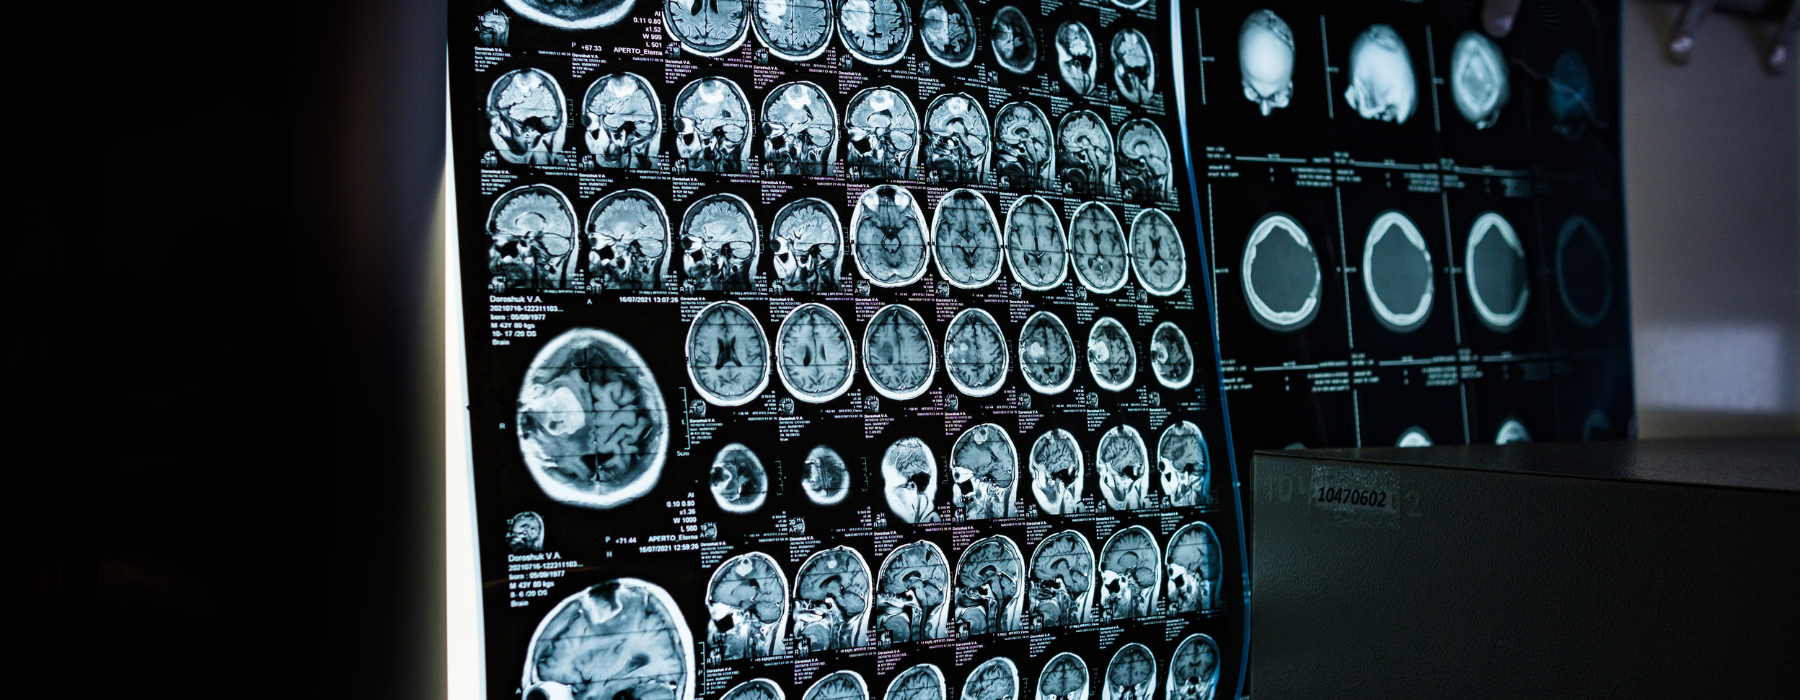

Painel com imagens de ressonância magnética cerebral mostrando diferentes cortes do cérebro para investigação de dor de cabeça e tontura. Exames de imagem como a ressonância magnética auxiliam na investigação de tontura persistente, dor de cabeça intensa e complicações relacionadas à pressão alta.

Os exames mais solicitados são a tomografia computadorizada (TC), especialmente em situações de urgência, e a ressonância magnética (RM), que oferece maior detalhamento das estruturas cerebrais.